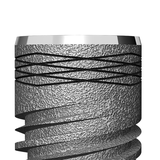

I55-4.2,8

• Шейка с насечками способствует улучшению остеоинтеграции.

• Двойная платформа с глубоким соединением с шестигранником и плоским соединением без шестигранника.

• Спиралевидная глубокая резьба.

• Биологическая совместимость материала – имплантаты обрабатываются фосфатом кальция, после чего их поверхность приобретает некоторую шероховатость, что, в свою очередь, положительно влияет н процесс остеоинтеграции.

• Стабильность имплантата обеспечивает апекс c неагрессивной геометрией.